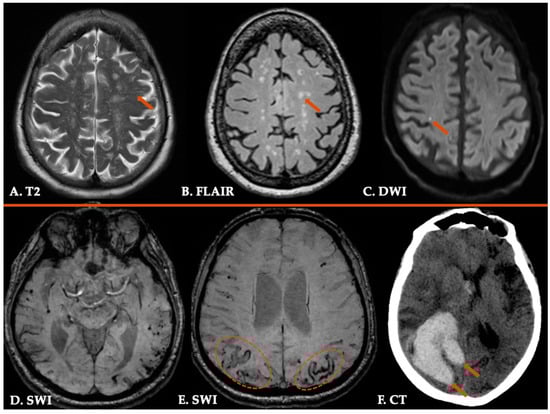

| 3. Probable CAA | Clinical data and MRI demonstrating the following: • Age ≥ 50 years • Presentation with spontaneous ICH, TFNEs, or CI/Dementia • ≥2 of the following strictly lobar hemorrhagic lesions on T2*-weighted MRI, in any combination: ICH, CMB, cSS/cSAH foci OR • 1 lobar hemorrhagic lesion + 1 white matter feature (Severe CSO-PVS or WMH-MS) • Absence of any deep hemorrhagic lesions (ICH, CMB) on T2*weighted-MRI • Absence of other cause of hemorrhagic lesions * • Hemorrhagic lesion in cerebellum not counted as either lobar or deep hemorrhagic lesion |

| 4. Possible CAA | Clinical data and MRI demonstrating the following: • Age ≥ 50 years • Presentation with spontaneous ICH, TFNEs, or CI/Dementia • Absence of other cause of hemorrhage * • 1 strictly lobar hemorrhagic lesion on T2*-weighted MRI: ICH, CMB, cSS/cSAH focus OR • 1 white matter feature (Severe CSO-PVS or WMH-MS) • Absence of any deep hemorrhagic lesions (ICH, CMB) on T2*-weighted MRI • Absence of other cause of hemorrhagic lesions * • Hemorrhagic lesion in cerebellum not counted as either lobar or deep hemorrhagic lesion |